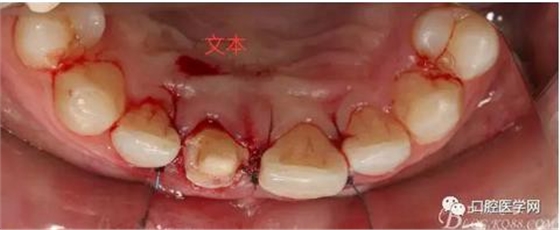

翻瓣 見(jiàn)11釉牙骨質(zhì)界存在,牙槽嵴頂?shù)接匝拦琴|(zhì)界不足2mm。21牙槽嵴頂?shù)接匝拦琴|(zhì)界不足2mm

去骨后,牙槽嵴頂?shù)接匝拦琴|(zhì)界達(dá)到2.5mm。保留11,21之間的牙槽嵴頂,不改變齦乳頭的狀態(tài)。

術(shù)后一周拆線